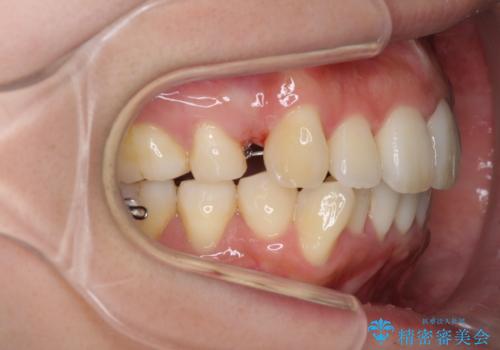

- リンガルブラケット

上顎の前から4番目の歯を両側抜歯して、上下裏側の装置で前歯を引っ込める計画としました。

裏側からの矯正であったため、表側に比べて少し治療期間を要しました。